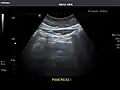

Abdominal Ultrasound (Full Exam)

STRUCTURED REPORT

(Technique: Transabdominal ultrasonography; Device: Toshiba Aplio XG)

Pancreas: Visualized portions unremarkable.

IMPRESSION:

Normal abdominal ultrasound.

Pancreas -